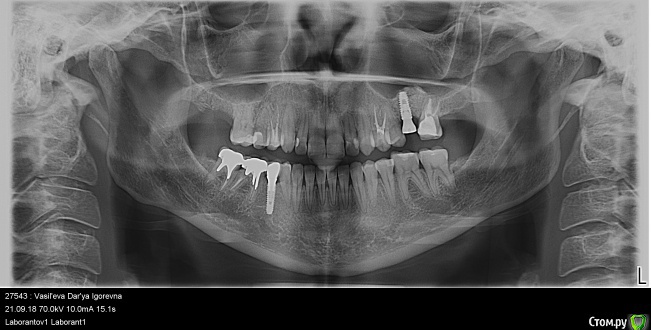

dentikl Опубликовано 5 октября, 2018 Поделиться Опубликовано 5 октября, 2018 Здравствуйте!. Они могут ..? Хотелось бы Ваше мнение.Здравствуйте.Могут но не факт.Панорамный рентген покажите?А по пунктам расскажите?(новый тест,аллерголог,гастроэнтеролог) Ссылка на комментарий

Туманская Опубликовано 5 октября, 2018 Автор Поделиться Опубликовано 5 октября, 2018 Здравствуйте.Могут но не факт.Панорамный рентген покажите?А по пунктам расскажите?(новый тест,аллерголог,гастроэнтеролог)Аллерголог сказал наблюдать. Тесты пока не переделывала. Сейчас симптомов нет. Языком не трогаю формирователь, боюсь. Снимок сейчас постараюсь прикрепить. У гастроэнтеролога была год назад, уже после всего, гастроскопия с пункцией ничего не показали. Гастрит как у всех, не более. Ссылка на комментарий

Туманская Опубликовано 5 октября, 2018 Автор Поделиться Опубликовано 5 октября, 2018 Панорамный снимок Ссылка на комментарий

Туманская Опубликовано 5 октября, 2018 Автор Поделиться Опубликовано 5 октября, 2018 Если не сложно, посмотрите, пожалуйста на зубы под коронками. Одон врач говорит, что все норм. Другой, что на 46м прилегание вкладки плохое и надо переделывать. Первый говорит, что убрать вкладку в моем случае не получится, потеряю зуб. При этом у меня есть боли неясные где-то в районе этих зубов, но точно определить не могу. Ставить новые коронки, если там не все гладко, тоже не хочется. Когда сняли старые, между зубами оказалась пролежень. Что делать дальше? Вкладки серебряные. Ссылка на комментарий

Дмитрий Л. Опубликовано 7 октября, 2018 Поделиться Опубликовано 7 октября, 2018 Если не сложно, посмотрите, пожалуйста на зубы под коронками. Одон врач говорит, что все норм. Другой, что на 46м прилегание вкладки плохое и надо переделывать. Первый говорит, что убрать вкладку в моем случае не получится, потеряю зуб. При этом у меня есть боли неясные где-то в районе этих зубов, но точно определить не могу. Ставить новые коронки, если там не все гладко, тоже не хочется. Когда сняли старые, между зубами оказалась пролежень. Что делать дальше? Вкладки серебряные.Кариес корня под вкладками. Пародонтальный карман и отсюда боли (дискомфорт).Надо переделать, но то, что зубы можно потерять от этой переделки, тоже правда. Решать вам.По поводу гальваноза от серебра: всё возможно, любые металлы могут создать гальваноз. Смотрите по самочувствию.Аллерготесты я бы не делал, лишняя трата времени и денег. Делайте из циркония. Ссылка на комментарий